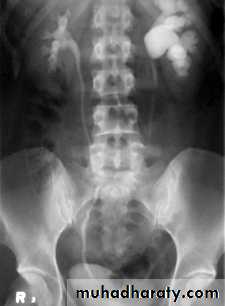

Infantile hydronephrosis ( PUJ OBSTRUCTION ):

IVU shows :

Marked dilatation of pelvis and may be extra-renal.

Calyceal dilatation is late and in advanced cases form foot shape PCS

The ureter is not seen and when it is seen looksnormal .

Delayed film with I.V. diuretic produce gross dilatation .